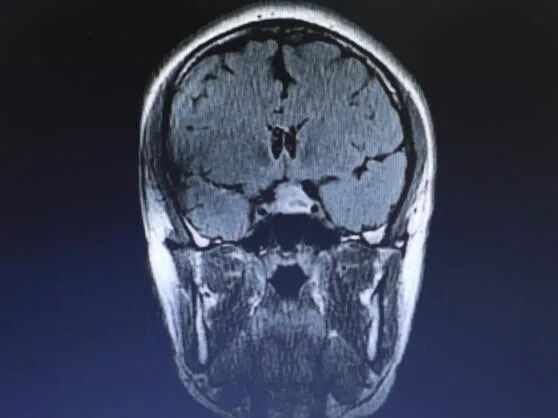

儿童用户 年龄9岁 左侧植入SYNCHRONY人工耳蜗

核磁检查原因:评估对侧能否植入耳蜗

影片清晰度很高,完全满足诊断和评估需求。

影片显示耳蜗侧有较小伪影存在,但对侧的听神经和耳蜗显示的非常清晰,小朋友的耳蜗和内听道完全没有问题,左侧大脑也没有问题,所以经过核磁报告评估,这个小朋友完全适合对侧人工耳蜗植入。